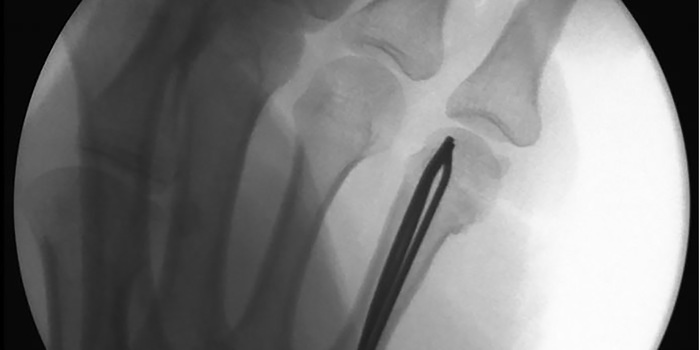

Mein linker Arm ist ein lebloses Stück Fleisch. Die Operation hat unterdessen begonnen. Der Chirurg schneidet und zieht die Drähte in die Hand. Ich fühle zwar absolut keinen Schmerz, aber es ruckelt in der Schulter. Zwischendurch hämmert er. Es macht mehrmals Klack Klack Klack. Und ich höre auch, wie der Chirurg die Drähte mit der Zange abkneift. Der Arm ist wie gesagt im Tiefschlaf und doch «spüre» ich, dass etwas in meinen Körper eindringt, was da nichts zu suchen hat. Es ist ein bisschen gruselig. Ich kann es nicht besser beschreiben.

«Alles gut?», will ich vom Chirurgen wissen. Soweit sei alles gut, meint dieser. Daumen hoch. Es seien einzig drei statt der ursprünglich geplanten zwei Kirschner-Drähte «verbaut». Naja, mehr ist immer besser. Der Chirurg kann sich ein Schmunzeln auf meine Bemerkung nicht verkneifen und meint nur: «In diesem Fall wäre weniger tatsächlich mehr».